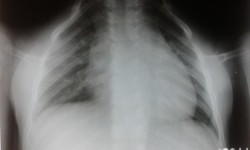

Asphyxiating Thoracic Dystrophy (Jeune Syndrome)

By Admin | September 30, 2013 - 12:37 pm | Musculoskeletal, Skeletal Dysplasias

Fig.1-Chest P.A